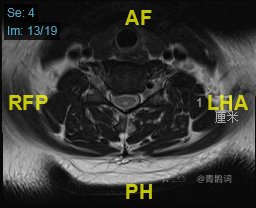

颈部磁共振平扫:

颈部磁共振平扫后增强: